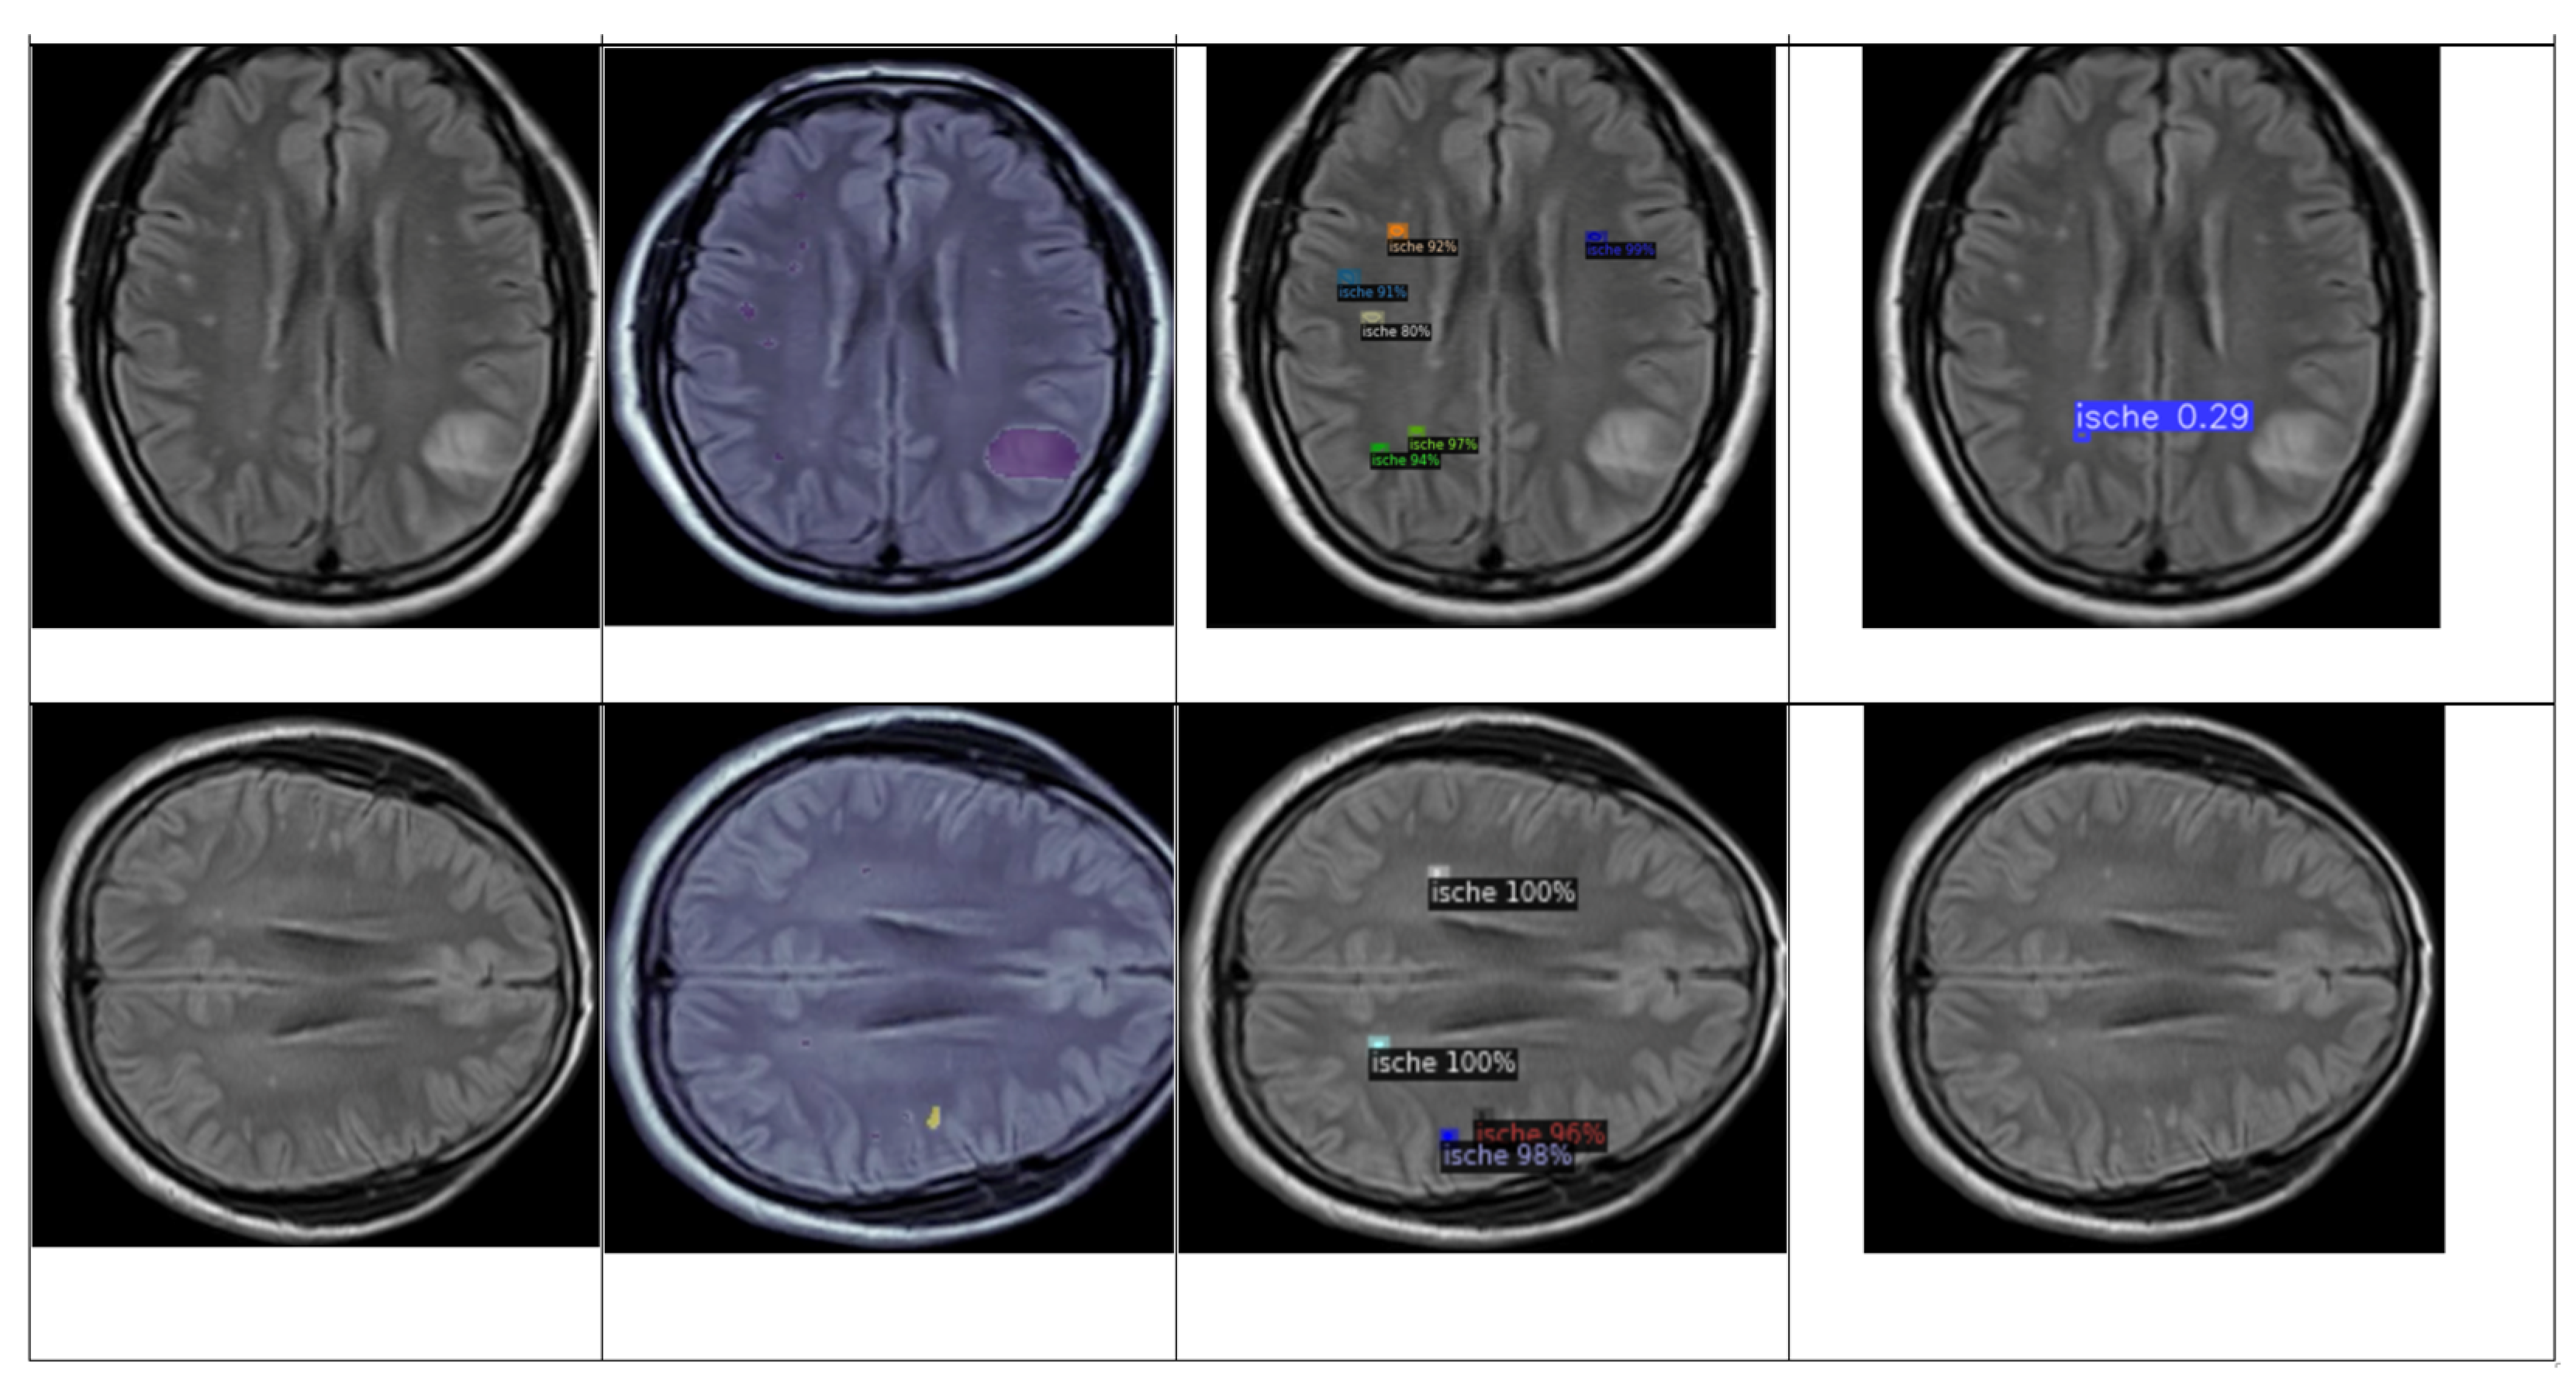

4.3. Detection and Classification

4.3.1. YOLOv8 Model for Detection and Classification

4.3.2. DETECTRON2 Model for Detection and Classification

4.5. Brief Comparison Results Between Expert Criteria and YOLO and Detectron2 Models for Classification of Ischemia and Demyelination Lesions